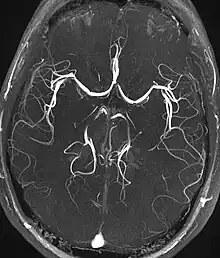

Magnetic resonance angiography (MRA) and venography | Time-of-flight | TOF | Blood entering the imaged area is not yet magnetically saturated, giving it a much higher signal when using short echo time and flow compensation. | Detection of aneurysm, stenosis, or dissection[31] | ![]() |

Magnetic resonance angiography

Magnetic resonance angiography (MRA) is a group of techniques based to image blood vessels. Magnetic resonance angiography is used to generate images of arteries (and less commonly veins) in order to evaluate them for stenosis (abnormal narrowing), occlusions, aneurysms (vessel wall dilatations, at risk of rupture) or other abnormalities. MRA is often used to evaluate the arteries of the neck and brain, the thoracic and abdominal aorta, the renal arteries, and the legs (the latter exam is often referred to as a "run-off").